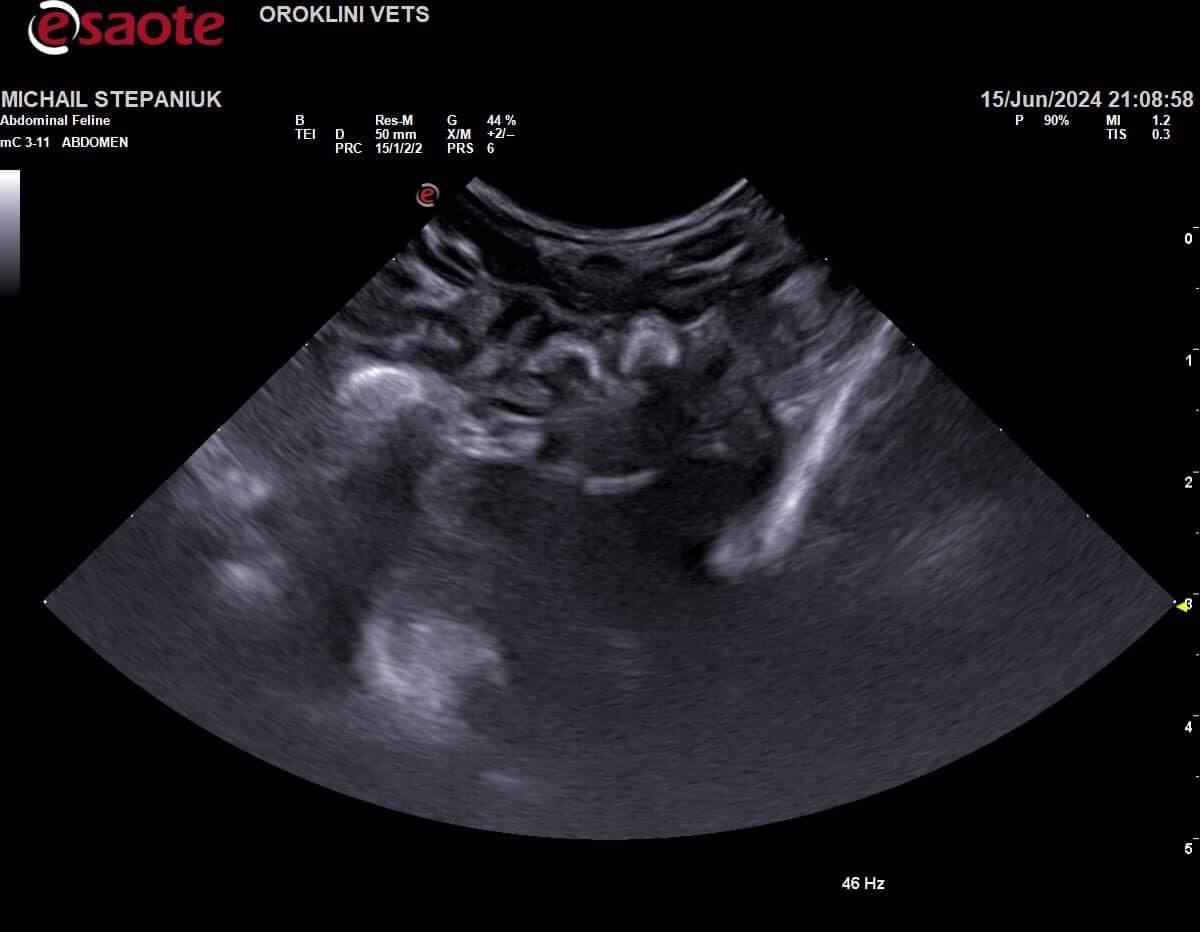

Нарушена перистальтика скорее всего, дело не в Кале, молоко не переходит из желудка дальше, а выходит обратно… надо узи. В ороклини пообещали принять, но уже 6:30, с 2 жду((( никто не пришел туда

Заворот желудка тоже может быть. На практике был один малыш,ему было пара недель вроде,заворот,оперировали и удачно,вырос в большого котэ🐈

Инородный предмет может быть?

Жидкие каловые массы могут обходить твердые, если не ошибаюсь, и твердые при этом все равно внутри остаются.